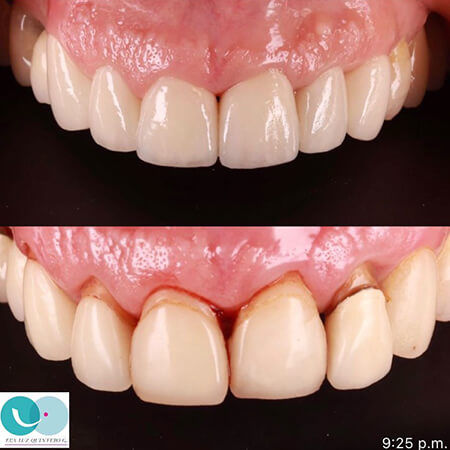

Eva Luz Quintero

Odontólogo Cali

Diseño de sonrisa y mejora de la salud gingival, realizado por la Dra. Eva Luz Quintero, odontóloga en Cali, Colomb…

Eva Luz Quintero

Odontólogo Cali

En este caso de antes y después, la Dra. Eva Luz Quintero, odontóloga en Cali, realizó el tratamiento de una pacien…